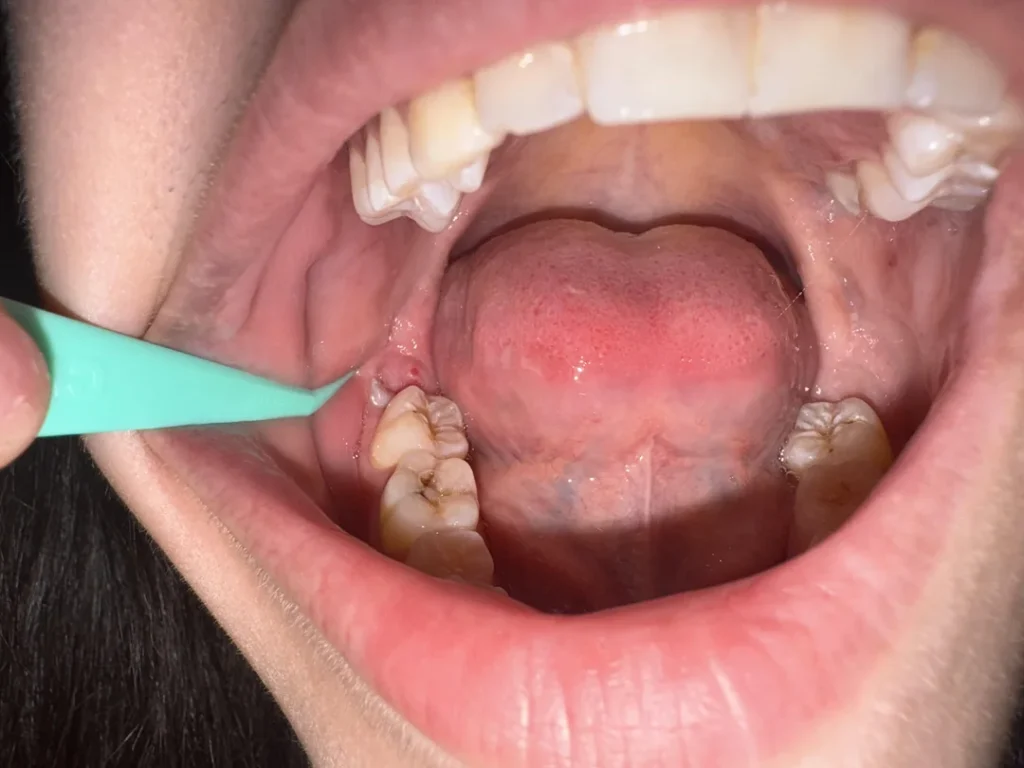

The third molars, commonly called wisdom teeth, are the final teeth to erupt, typically between the ages of 17 and 25. While some people are lucky enough to have them emerge without any issues, for many, these teeth can become a significant source of discomfort and a threat to overall health. The most common reason for a wisdom tooth removal brampton is that they become impacted. An impacted wisdom tooth is one that doesn’t have enough room to grow in properly and is stuck in the jawbone or under the gum tissue.

The problems associated with impacted wisdom teeth are numerous and can become serious if left untreated:

- Pain and Pressure: An impacted or partially erupted wisdom tooth can cause intense pain and swelling. The tooth’s pressure against the neighboring

molarcan also lead to discomfort and discomfort in the surrounding teeth. - Infection and Gum Disease: When a wisdom tooth partially erupts, it creates an opening for

bacteriato enter around the tooth. This can lead to a localized infection called pericoronitis, which is characterized by redness, swelling, and pain. Over time, this can progress to more serious gum disease or periodontal disease. - Tooth Decay: Because they are so far back in the mouth, wisdom teeth are often difficult to clean. This makes them highly susceptible to tooth decay and the formation of decay. The hard-to-reach area can also be a breeding ground for germs and other contaminants.